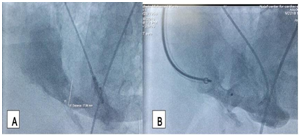

Figure 2 critical mid left anterior descending artery stenosis (A) that successfully managed with xience stent 2" 14mm (B).

Figure 3 Left ventricular angiography (LAO/Cranial 35/35) before (A) and after (B) transcatheter closure of ventricular septa! repture with 20mm 13l MVSD device, small residual shunt was detected.